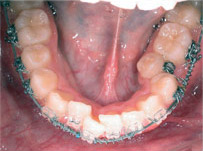

向外暴出

牙齒向外暴出藉由矯正得到適當的改善:

Before

After